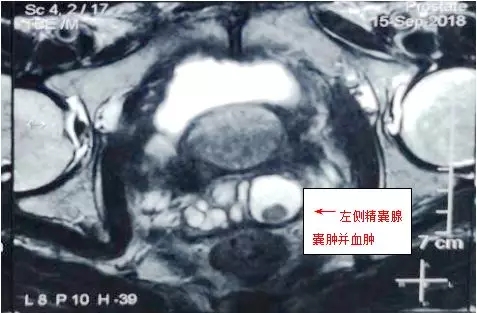

精囊镜微创手术是目前国际上最新开展的男科手术之一。近日,我院泌尿外科成功为一例不明原因反复血精的患者实施了精囊镜检查,手术取得了预期的疗效。

患者,男性,57岁,因反复血精入住我院泌尿外科。经科内讨论,行相关检查,明确手术指征后为患者实施了经尿道射精管切开术(TURED)+经尿道精囊镜检查术,手术过程顺利,术后患者恢复良好,已痊愈出院。

精囊镜检查是用一根细的内窥镜(如超细输尿管镜)通过射精管进入精囊腔,循正常的精道解剖途径逆行依次检查射精管和精囊,如发现病变可同时在镜下处理(如结石则可行钬激光碎石,息肉则可取活检等),是治疗血精、无精、不育症等男性疑难疾病的先进技术,已成为诊断治疗血精、射精痛、精囊炎、精囊结石、射精管梗阻性无精子症等精道疾病的新武器。该技术安全性高,疗效好,创伤较小,并发症发生率低,操作简便,在镜检的同时能达到治疗的目的。